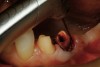

Figure 15  After removal of the defective restoration, it can be seen clinically that the margin of the preparation on the distal of tooth No. 21 was extremely subgingival. The surrounding periodontium was inflamed and hemorrhagic. The laser was used to perform apical repositioning of the bony crest using a closed-flap technique.

Figure 15